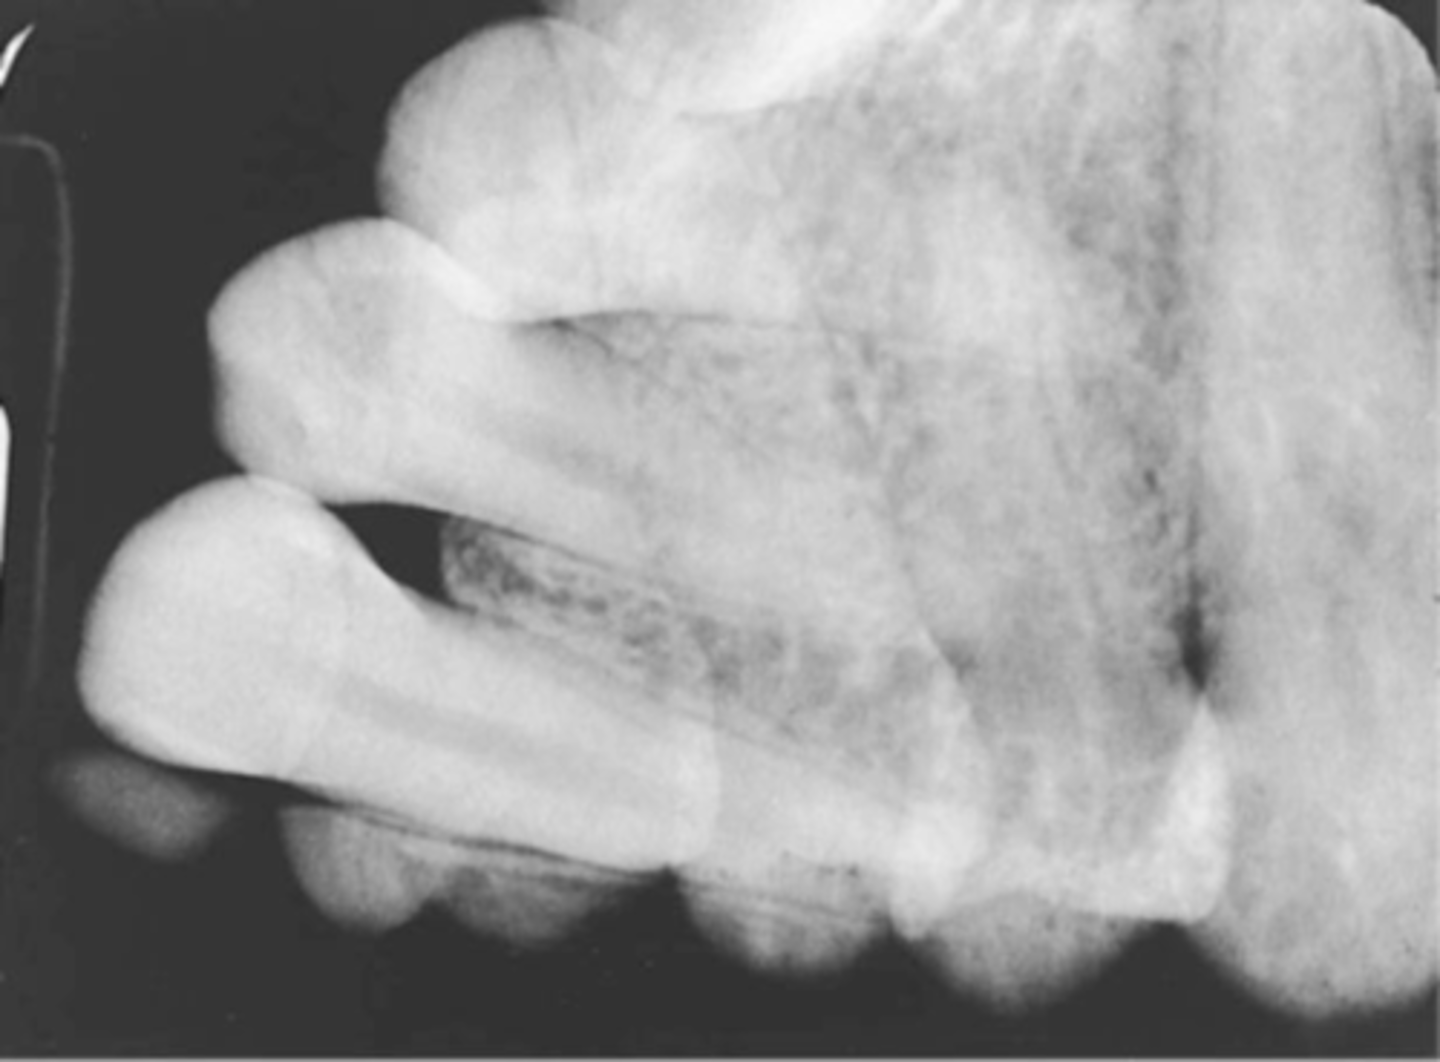

Incorrect Vertical Angulation-->Elongated Images

-Teeth appear long and distorted

-Vertical angulation was insufficient or too flat, resulting in images that are longer then the actual teeth.

-Occurs more often with the bisecting technique

-To prevent use adequate vertical angulation

Tube Head & PID-->Elongation of the Image

-Bisecting technique error

-Insufficient Angulation (not steep enough), causing elongation or increased anatomy of the teeth and cutting off apex.